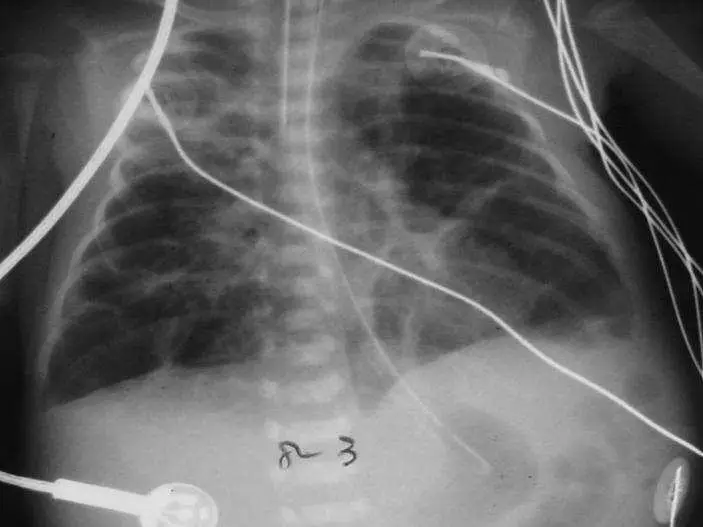

下圖為一孩童之胸部 X光素片,最可能的診斷為:

從此孩童正位胸部 X 光片可觀察到:

- 雙側肺野呈現非均質性的網狀(reticular)及粗大支氣管紋理增粗影,夾雜多處圓形或不規則之相對透明區。

- 肺野輕度過度膨脹(hyperinflation),肋膈角鈍化且橫膈略呈平坦。

- 無明顯單側實質塌陷或實質性大片致密影,也不見典型的空氣支氣管徵。

- 無游離空氣徵象,如肺外空氣或皮下氣腫。

- 影像中可見多條導管,暗示嬰兒曾接受長期呼吸支持。

這些特徵符合慢性肺損傷晚期(Stage IV)時期常見的「網狀纖維化+局部囊狀腔室」及「過度充氣」表現(radiopaedia.org)。